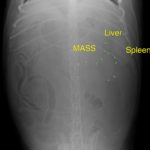

エコーでは脾臓と肝臓にMASSを確認。

開腹すると脾臓と肝臓に腫瘤病変があり破裂、出血していました。